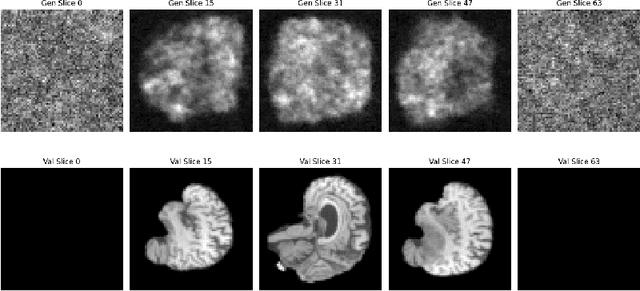

Abstract:Diffusion models have recently gained state of the art performance on many image generation tasks. However, most models require significant computational resources to achieve this. This becomes apparent in the application of medical image synthesis due to the 3D nature of medical datasets like CT-scans, MRIs, electron microscope, etc. In this paper we propose a novel architecture for a single GPU memory-efficient training for diffusion models for high dimensional medical datasets. The proposed model is built by using an invertible UNet architecture with invertible attention modules. This leads to the following two contributions: 1. denoising diffusion models and thus enabling memory usage to be independent of the dimensionality of the dataset, and 2. reducing the energy usage during training. While this new model can be applied to a multitude of image generation tasks, we showcase its memory-efficiency on the 3D BraTS2020 dataset leading to up to 15\% decrease in peak memory consumption during training with comparable results to SOTA while maintaining the image quality.